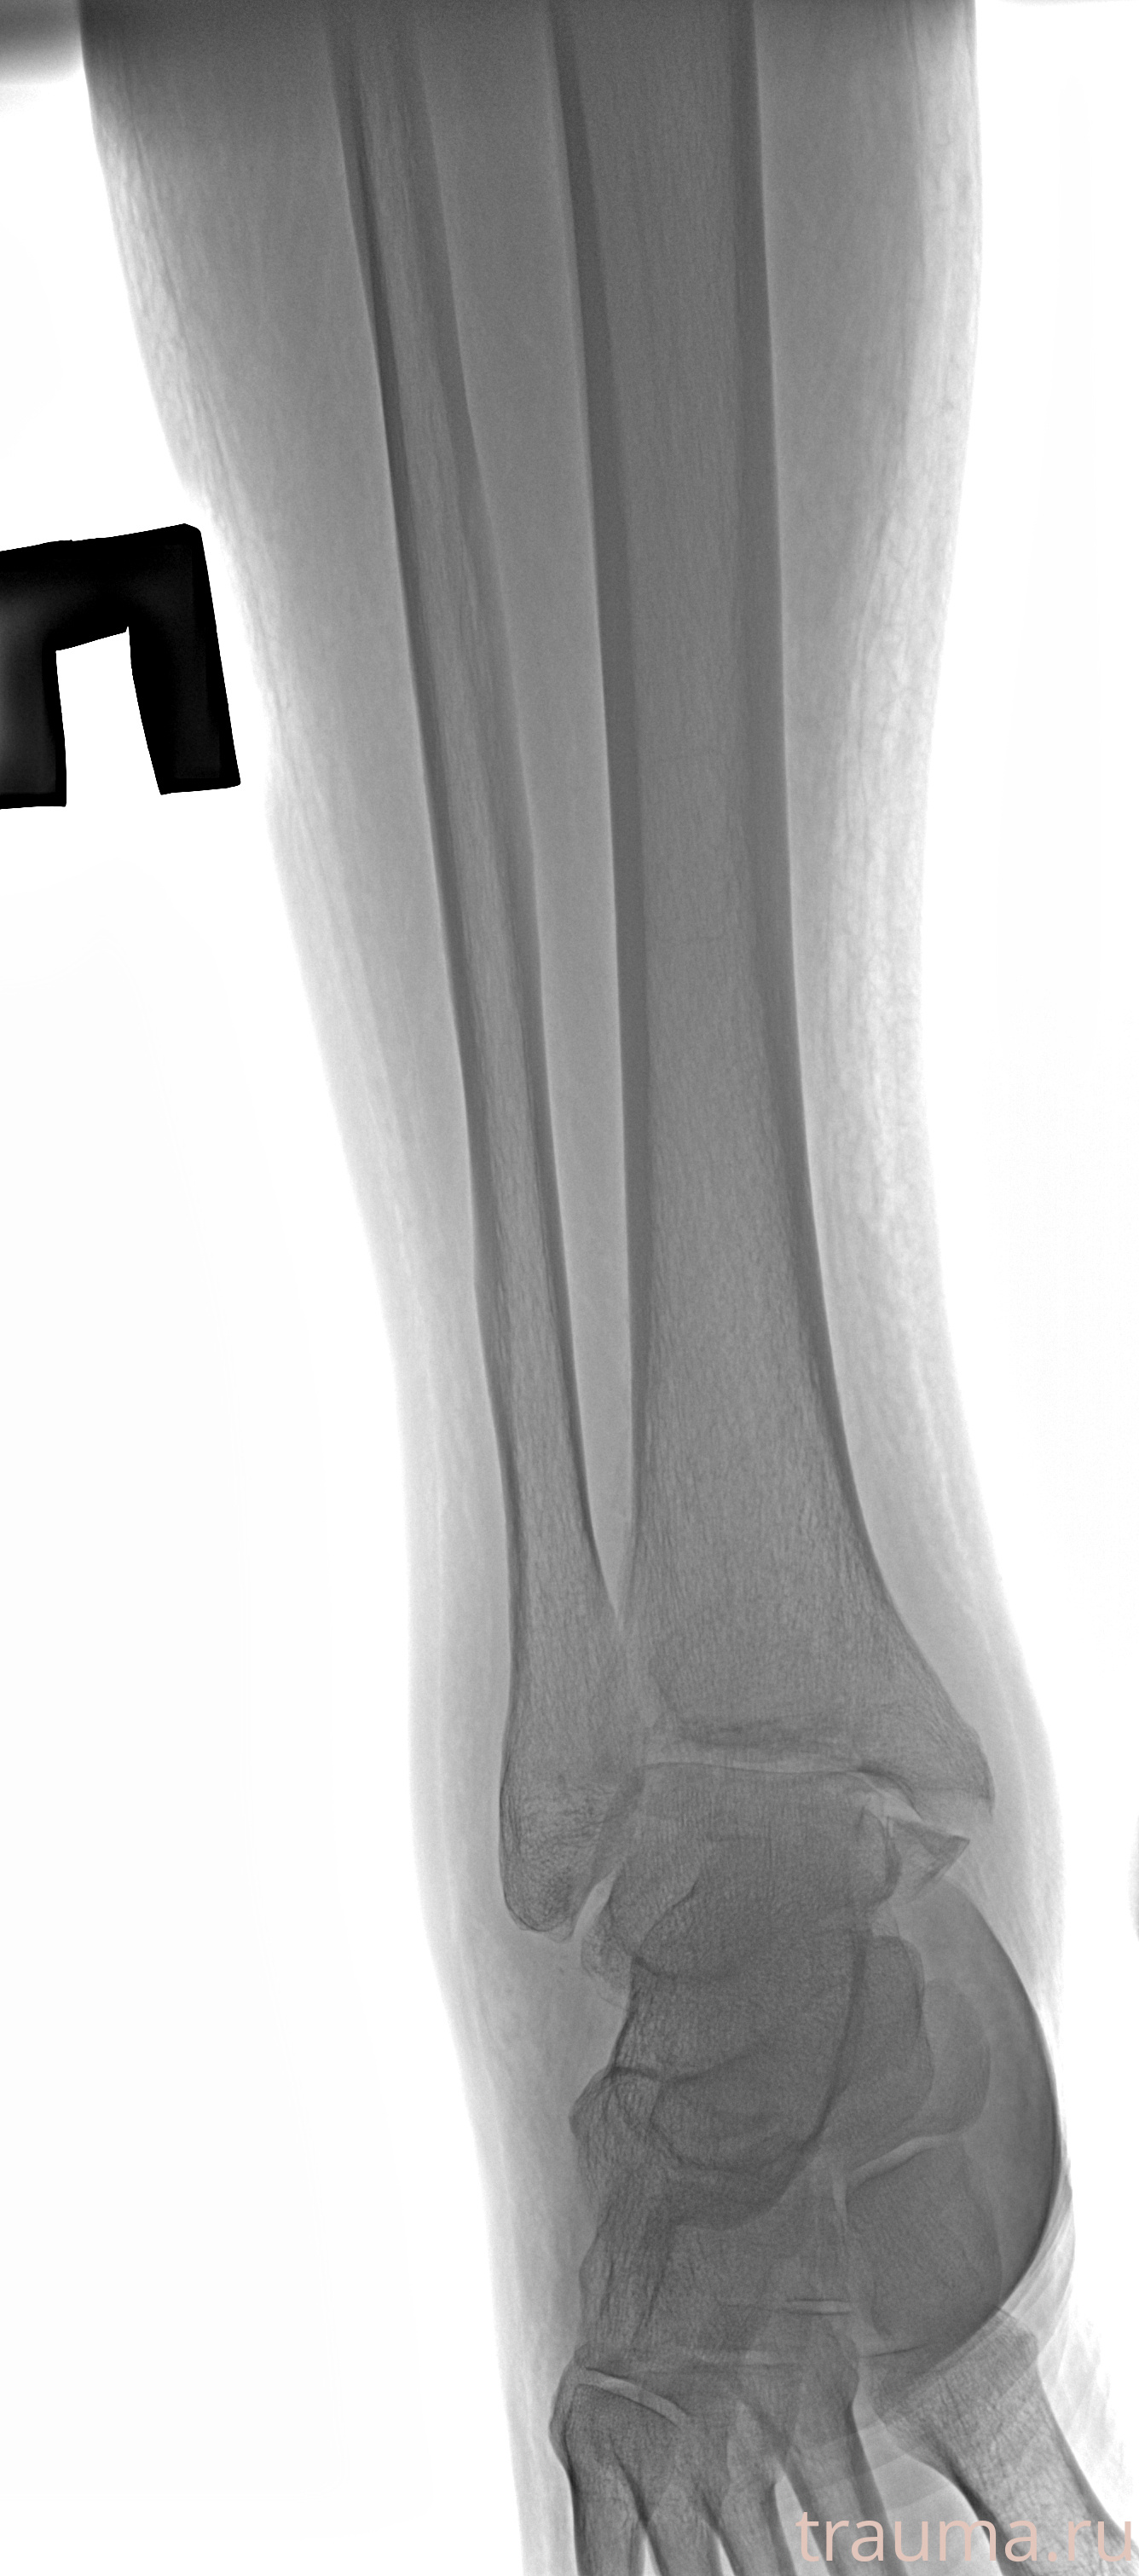

Рентгенограммы

Рентген на дому: по вашему адресу приезжает врач-рентгенолог, травматолог-ортопед с мобильным рентгеновским аппаратом, проводит диагностику травмы или заболевания, делает необходимые рентгенограммы, дает рекомендации по дальнейшему лечению. Получить качественные снимки в домашних условиях возможно благодаря уникальной методике, разработанной МосРентген Центром для института  Склифосовского